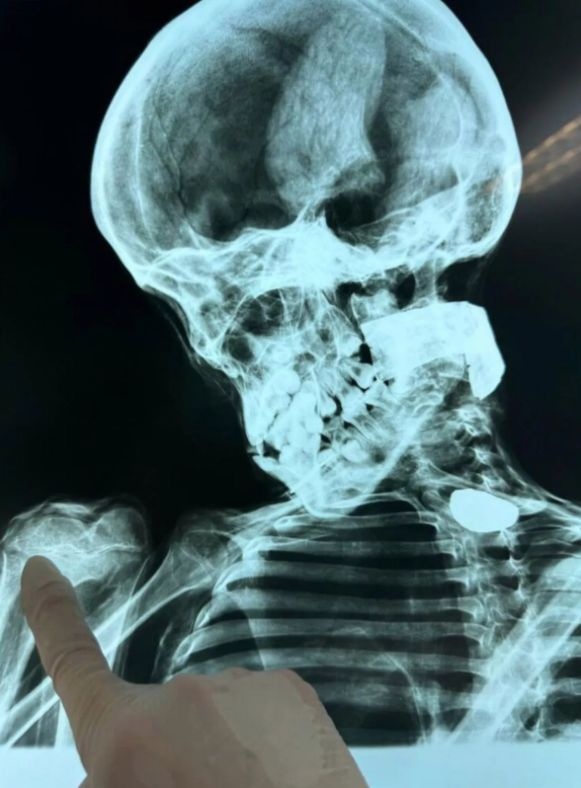

Μιλώντας στον Μεξικανό δημοσιογράφο Jaime Maussan, ο Mantilla είπε ότι ανυπομονούσε να παρουσιάσει όλες τις εξελίξεις και τις τελευταίες πληροφορίες για τα πτώματα. Είπε ότι τα όντα έχουν υποβληθεί σε αξονική τομογραφία και πρόκειται να αποκαλύψουν όλες τις εκπλήξεις και τα νέα την ημέρα της ακρόασης.

Μιλώντας για το πιο πρόσφατο δείγμα είπε: «Είναι ένα εντυπωσιακό δείγμα στο οποίο είχα πρόσβαση μόλις πριν από λίγες μέρες. Παρατηρήσαμε ότι τα χαρακτηριστικά αυτού του δείγματος είναι πολύ, πολύ ιδιαίτερα. Στα πόδια είδαμε ότι η αναλογία μεταξύ των δακτύλων και του πέλματος του ποδιού είναι πολύ μεγαλύτερη από οποιαδήποτε άλλη. Παρουσιάζουμε τα στοιχεία στην επιτροπή πολιτισμού, συνέδρια από διαφορετικές εθνικότητες που ανέλυσαν τα σώματα. Αυτή, πιστεύω, είναι μια από τις πιο σημαντικές ανακαλύψεις, όχι μόνο στην ιστορία του Περού, αλλά στην παγκόσμια ιστορία προέρχεται από τα εδάφη του Περού, αλλά είναι μια κληρονομιά που ανήκει στην ανθρωπότητα και όλοι έχουμε το δικαίωμα να γνωρίζουμε την απάντηση και την προέλευση αυτών των όντων. Αυτό που πρόκειται να απαιτήσουμε στο Περού, και μέσω του Κογκρέσου σε αυτήν την ακρόαση, είναι να ξεκινήσει μια διεθνής έρευνα. Δεν υπάρχει κανένας φόβος, δεν πρέπει να φοβούνται γιατί υποστηρίζονται από την επιστήμη».